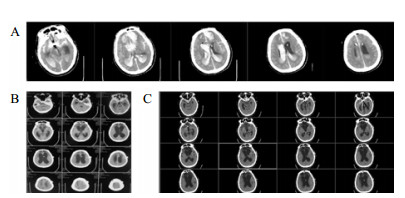

1 资料与方法病例1, 女,24岁,2015年12月以“脑干出血破入脑室术后1年,脑积水V-P分流术后”入院。入院时为植物状态,GCS 8分,双瞳孔3.0 mm, 对光反应灵敏,双侧巴氏征阳性;V-P分流调压阀压力为1.0(Medtronic, Minnesota, USA),储液囊外接引流管,压力为外耳道连线上方10 cmH2O (1 cnH2O = 0.098 kPa)。诊断为:脑干出血术后、脑积水、永久性植物状态(图 1)。

| A:2014年12月2日CT;B: 2015年12月8日入院CT,分流压力为1.0 图 1 病例1 CT |

将分流管压力降为0.5后的第6天,该患者复查头颅CT和意识水平均无明显改变;后经分流储液囊穿刺脑脊液外引流,每日引流量150 mL,持续10 d,仍无明显改变。再将脑脊液外引流量增至300 mL/d,患者行为学稍有变化,开始出现刺激后头部转动、手部摸索活动,眼球能视觉追踪。复查头颅CT示脑室形态略缩小。因此,在此基础上再次手术将分流管由原来的抗虹吸可调压管更换为非抗虹吸可调压管,压力设为1.0。患者意识水平进一步改善,术后第4天复查CT示脑室较前缩小(图 2),其大小形态接近正常。随访一年,患者生活能自理,E-GOS 5分。

| 图 2 病例1更换分流管后第4天头颅CT |

病例2,女,60岁,2017年10月以“动脉瘤夹闭和脑内血肿清除术后6个月,意识进行性下降2个月余“入院。入院时植物状态;查体:GCS 8分,双瞳孔3.0 mm,对光反应灵敏,双侧病理征阴性。右侧额颞部颅骨缺损大。入院头颅CT示脑室扩大。诊断为:右前交通动脉瘤术后、脑积水、头皮下积液、右额颅骨缺损、持续性植物状态(图 3)。

| 右侧额颞部颅骨缺损7 cm×9 cm,双侧脑室和三脑室扩大 图 3 2017年10月12日病例2的CT |

入院后于2017年10月30日行“颅骨修补+V-P分流术”。术后将分流管压力逐步调至0.5。患者术后意识无明显改善,复查CT示脑室仍显著扩大。观察2周后病情同前,遂将储液囊外接引流,每日引流量约200 mL,持续3 d,未见行为学及影像学明显变化。加大引流至每日300 mL,持续3 d后,患者自主睁眼增多;引流量增至每天400 mL左右,患者能呼唤下睁眼和视觉追踪。而停止脑脊液外引流后,患者则退步到引流前水平。决定通过按压储液囊促进脑脊液引流(按压600次/d),持续10 d后,睁眼时间延长但仍无意识。考虑到患者意识水平和引流量明显相关,增加按压储液囊频率至1 500次/d,患者又能呼唤睁眼,但CT未见脑室明显缩小。随后增加按压至2 000次/d时,偶尔能出现遵嘱活动,复查CT示脑室结构较前稍有缩小,但脑室仍显扩张。动态观察患者的行为学变化和反复CT随访,逐步升至4 000次/d,患者可表达简短言语,但脑室仍略扩大。随后每月按压次数递增1 000次直至6 000次,复查CT示脑室结构明显缩小(图 4A);患者意识显著改善,能简短正确对答。2018年6月病情稳定后,逐渐减少到3 000次/d, 并复查头颅CT(图 4B)。患者意识完全恢复,交流言语思路清晰,搀扶能行走。

| A:2018年3月27日头颅CT,此时6 000次/d,脑室系统明显缩小;B:2018年9月15日头颅CT,3 000次/d 图 4 病例2头颅CT |

病例3,患者男,76岁,因“突发头痛昏迷,动脉瘤栓塞脑室引流术后半年余,脑积水分流术后3个月”入院。入院体查:GCS 7分,植物状态,双巴氏征阳性。V-P分流调压阀压力为1.0,脑积水虽已行分流术,但脑室仍明显扩大。拟诊:左前交通动脉瘤栓塞术后,脑积水V-P分流术后,持续性植物状态。脑室压力低于外耳道连线5 cm, 持续外引流脑脊液100~200 mL/d,同时去枕卧位,腹带加压包扎,适当增加补液量和扩脑血管改善脑微循环,力求增加颅内压和脑顺应性。脑室压力逐渐上升,然后调压至0.5,期间多次复查未见脑室大小明显缩小;但患者出现对威胁有眨眼反应,偶尔能对视觉对象定位,转为微小意识状态。发病4年后,即80周岁时,因为肺部感染而再次入院,控制肺部感染期间,考虑脑室仍扩大状态,予按压分流阀600次/d,患者意识显著上升,能主动要求饮食并表达喜好,能和家属互动做简单游戏。随访头颅CT见脑室较前有所缩小(图 5C)。

| A:第一次入院CT(脑出血栓塞和脑室外引流后);B:常规治疗后脑室扩大仍明显;C:2018年7月5日随访 图 5 病例3 CT |

病例4,男,26岁,因“车祸致颅脑损伤昏迷6个月”而入我院。急诊行开颅血肿清除术后1个月因脑积水而行V-P分流术。入院体检:GCS 7分,植物状态,四肢肌张力高,双巴氏征阳性。入院诊断为:重型颅脑损伤术后,脑积水V-P分流术后,持续性植物状态(图 6A)。考虑V-P分流过度引流,将分流调压阀调至最高的2.5水平,骨窗压力和头颅CT没有明显改变。遂将分流管皮下缝扎完全阻断,骨窗压力逐渐升高,术后复查CT(图 6B), 同时患者意识水平改善至微小意识状态。因脑积水加重再行V-P分流术,并择期予右额颞颅骨修补重建,随访头颅CT见图 6C。随后患者恢复至GCS 15分。

| A:男,26岁,颅脑损伤术后6个月入院时头颅CT;B:2015年1月4日分流管缝扎后CT;C:2017年3月8日V-P分流和颅骨修补术后 图 6 病例4 CT |